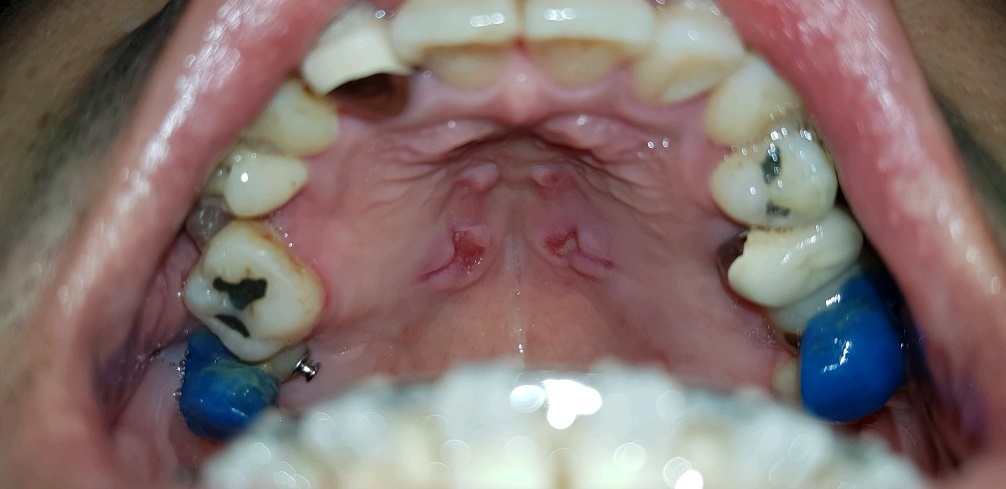

위 사진이 입천장에 작은 나사 4개를 박아서 입천장에 단단히 고정된 상태로 중앙에 나사 돌리는 곳이 있는데 쇠붙이같은걸 끼워서 양쪽 어금니 포함 4개를 쇠의 힘으로 조금씩 벌어지게 해서 치아들의 자리를 잡는 과정.

이걸 박고나서 일주일정도 고통이 지속됬던 것 같다.

(처음 몇일은 잠을 못잘 정도로 드럽게 아팠다;;)

입천장과, 쇠철판? 부분을 살짝 띄워놔서 공간이 있는데 양치하거나, 가레침이 들끓을 때 가레도 잘 못뱉고, 밥먹을 때도 온갖 음식물들이 다 끼게된다.

이 장치는 1년5개월 정도 후 제거했다..